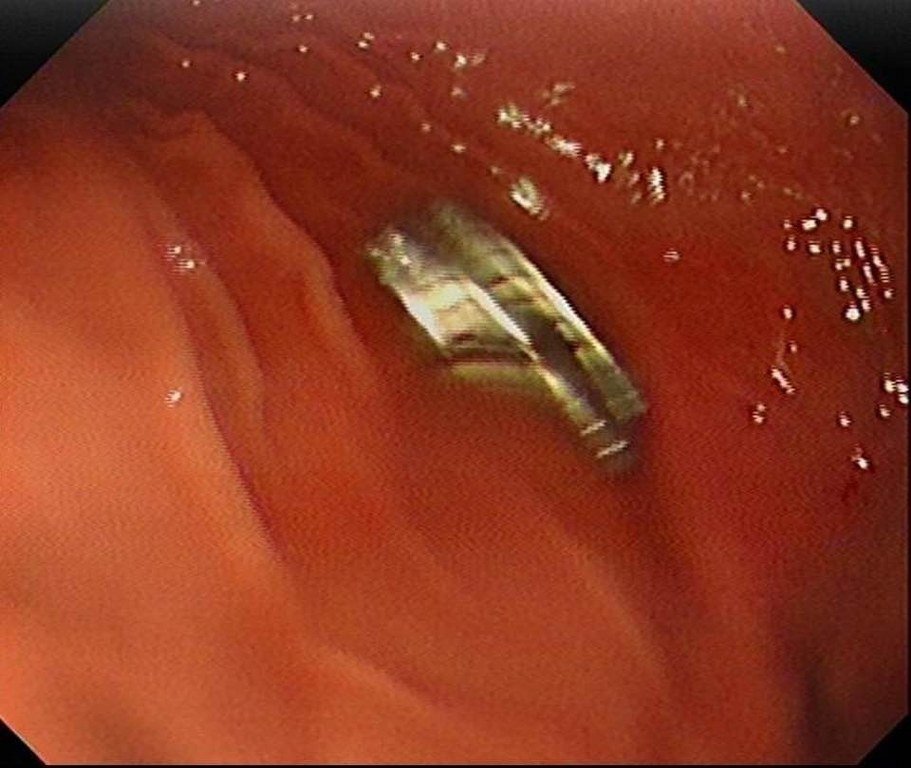

Edinilen bilgiye göre, Erzurum’da bir çocuk evde bulunan 19 tane mıknatısı yuttu. Çocuğun rahatsızlanması sonucu durumu öğrenen aile hastaneye başvurdu. Daha sonra çocuk Elazığ’a sevk edildi. Fırat Üniversitesi Çocuk Gastroenteroloji Hepatoloji ve Beslenme Bilim Dalı Başkanı Prof. Dr. Yaşar Doğan, çocuk hastanın yemek borusuna yapışmış 19 mıknatısı endoskopik yöntemle çıkardı.

Mıknatıslar uzun süre yemek borusunda takılı kaldığı için yemek borusu ve mide girişinde zedelenmeler olurken, çocuğun sağlık durumunun iyi olduğu ve taburcu edildiği öğrenildi.(İHA) -